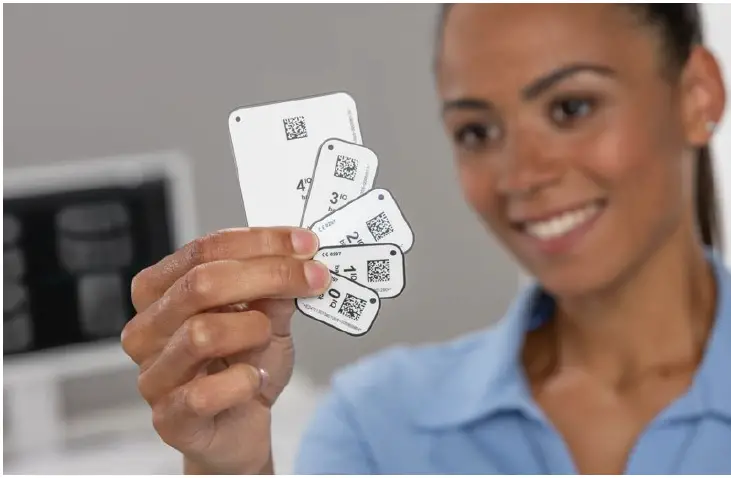

The VistaScan Mini Easy 2.0 works with VistaScan IQ image plates to ensure that it lives up to its full potential. Alongside the tried-and-tested technology and outstanding image quality, this combination offers a wide range of new features that noticeably improve user-friendliness, efficiency and reliability.

The scope of delivery includes everything you need to scan IQ image plates in sizes 0 and 2.